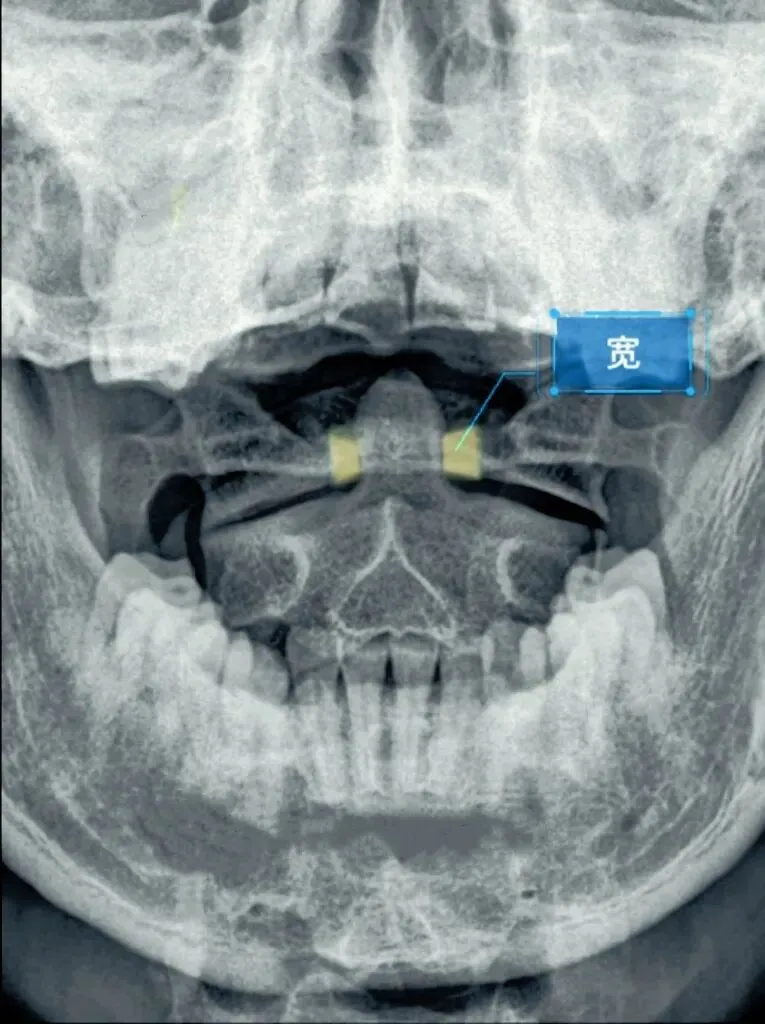

十张口是指寰枢椎的结构和位置关系,我们主要观察寰齿间隙和寰枢关节间隙及寰椎侧块的大小,来判断寰枢关节有无脱位的情况。

首先是寰齿间隙,如果枢椎与颈三的棘突位于同一条直线,

那么寰齿间隙哪边宽,就代表寰椎向哪边发生了侧方移位。

如果不在一条直线上,那就代表枢椎也有侧向的移动或旋转。

接下来是寰枢关节间隙,也称寰枢外侧关节,主要看两侧间隙是否等大,

如果一边宽一边窄,就代表寰椎向窄的一方发生了侧向倾斜。

再下来看寰椎侧块的大小,正常情况下侧块两边的宽度是等大的,

如果哪边侧块变大,就代表哪边的侧块向前方发生了旋转。